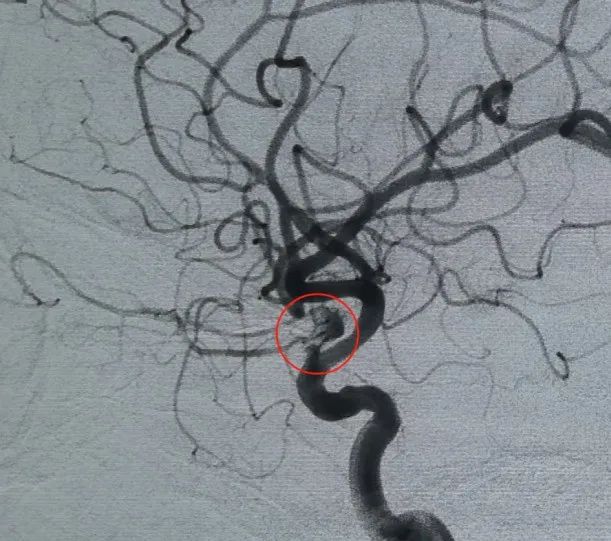

Diagnose: Aneurysma der linken inneren Hals schlag ader C6-Segment der Augen arterie

Der vaskuläre Zugang wurde über eine Punktion der Oberschenkel arterie und einen Perdenser hergestellt®Die 6mm × 20 cm große 3D-Spule wurde zuerst eingesetzt, um einen Korb zu bilden, eine stabile Wand zufuhr zu erreichen und eine sichere intra sacculare Unterstützung zu bieten. Es folgte das Einsetzen eines Perdenser®6mm × 15 cm 3D-Spule, um den Blutfluss innerhalb des lobulierten Tochter sacks zu stören.

Ein Perfiller®3mm × 6 cm ausdehnbare Spule und ein Perfiller®3mm × 2 cm dehnbare Spule wurden dann platziert, um den Hals verschluss abzuschließen. Anschließend wurde ein Nuva®Der Durchfluss diverter (TJED-D. 0-16) wurde abgegeben und über den Aneurysma hals eingesetzt. Die Follow-up-Angiographie sowohl in antero posterioren als auch in lateraler Sicht bestätigte eine hervorragende Abdeckung, eine gute Wand zuführung und eine klare Strahl kraft mit deutlicher Kontrasts tag nation.